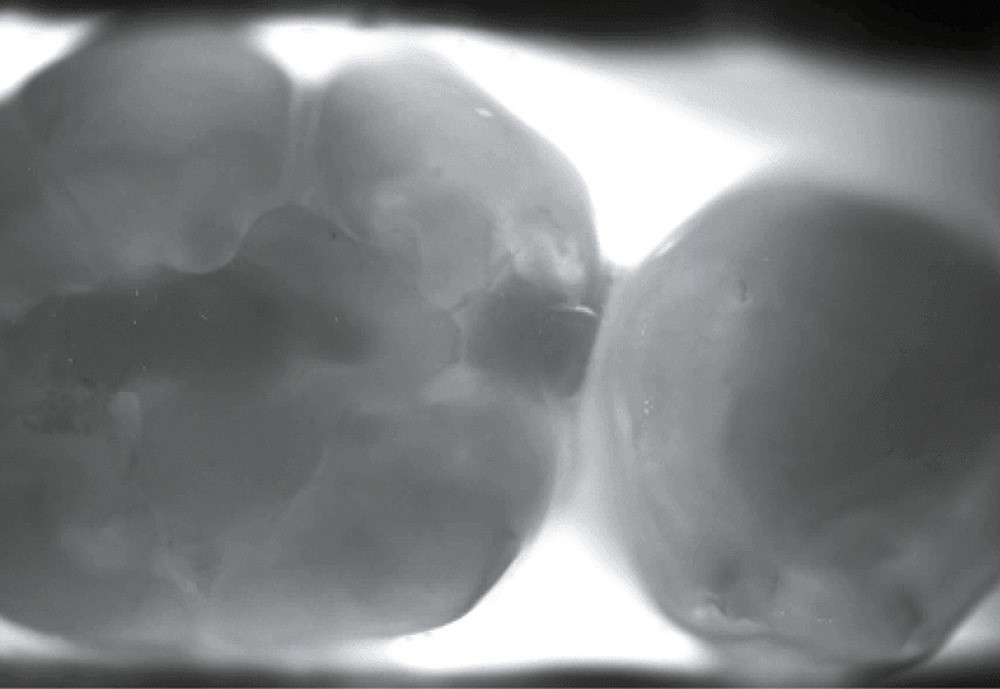

Planmeca, avec Emerald S, permet, avec un embout dédié, une détection par transillumination (fig. 2a et 2b).

Détection de carie par transillumination

Le principe repose sur l’envoi d’un faisceau lumineux infrarouge sur la dent.

L’émail d’une dent étant transparent, la lumière ne sera stoppée que dans les zones rendues opaques par le changement de structure minérale de cet émail : la carie (fig. 4).